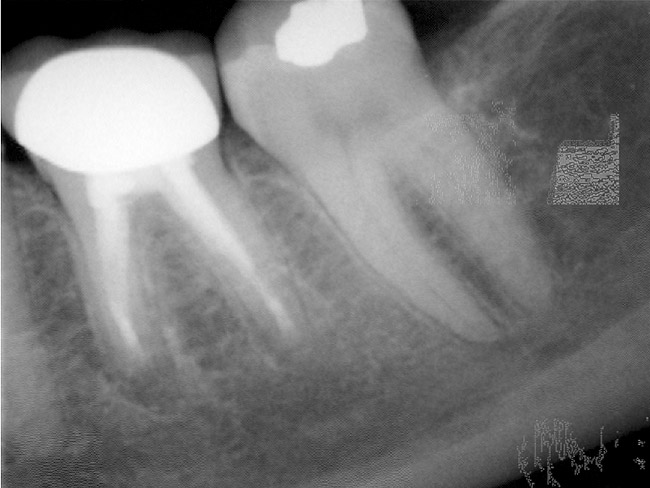

Figure 4b  The patient was asymptomatic, and periodontal probing depths were within normal limits; however, a new crown restoration was planned. Nonsurgical endodontic re-treatment was initiated. The intracoronal picture shows the previously treated 4 canals with infected gutta-percha filling.

Figure 4b

Figure 4c  Under high magnification, a furcation canal (Figure 4C) and a third distal canal (Figure 4D) were located.

Figure 4c